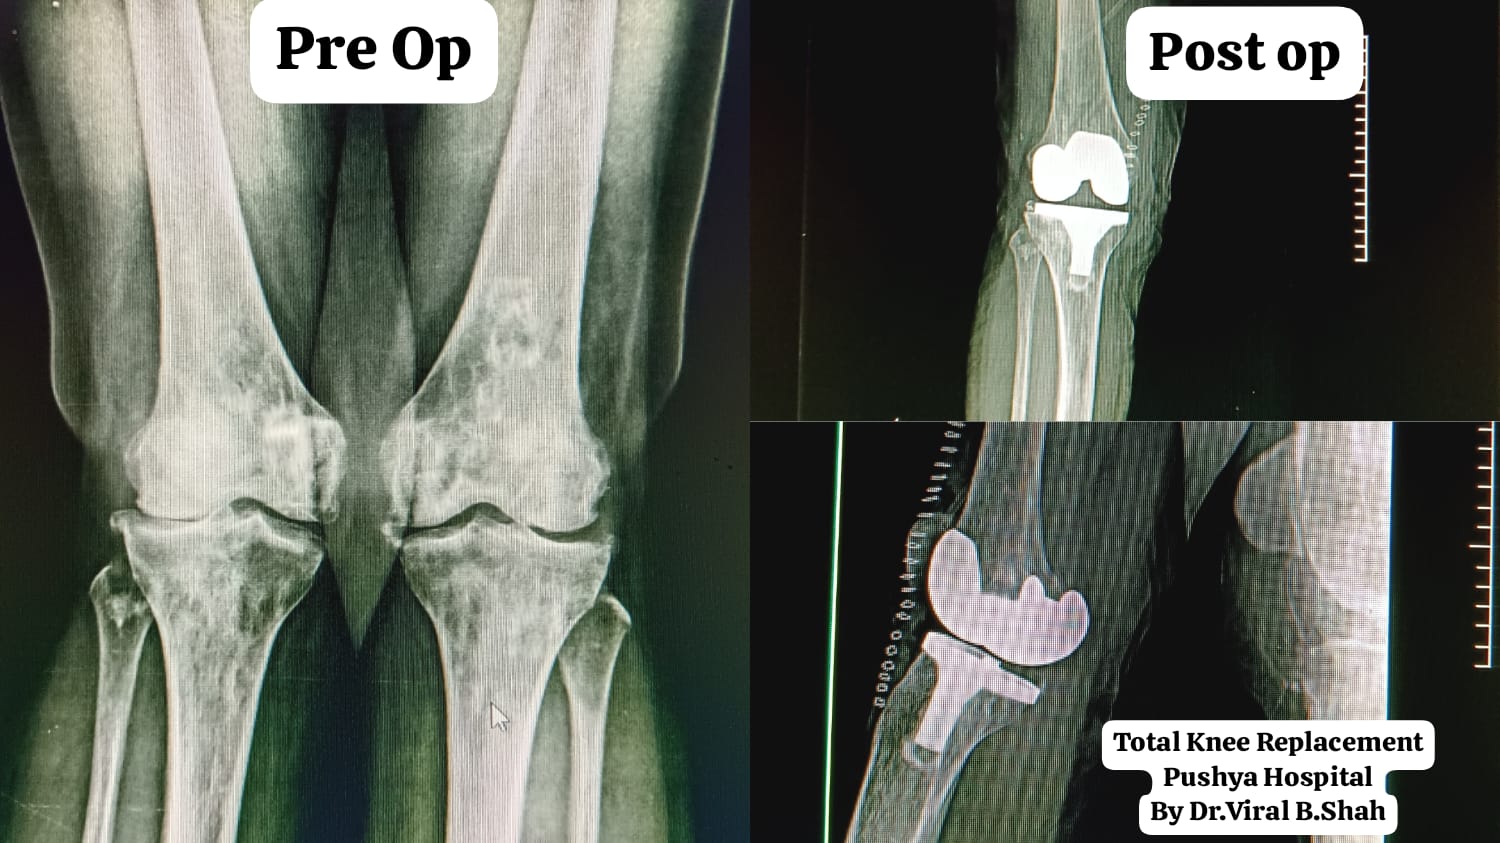

Joint Replacement Surgery